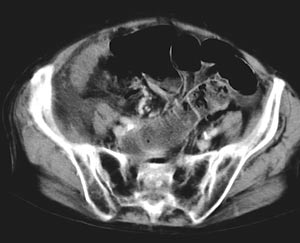

I motsetning til røntgen oversikt abdomen viste abdominal CT multiple luftvæskespeil i tynntarmen. Tynntarmslyngene var til dels moderat utspilte med diameter på om lag 3 cm (fig 1). Bak cøkum kunne man følge en slynge som ble innsnevret i forløpet, som ved obstruksjon. I tynntarmens videre forløp så man veggfortykkelse, økt kontrastoppladning i mukosa og halotegn. Mesenteriet viste stuvning og påfallende konvergens med antydet rotasjon som en virvel (whirl-sign, (fig 2, fig 3).

Funnet var forenlig med strangulasjonsileus, og indikasjonen for operativ behandling var nå åpenbar.